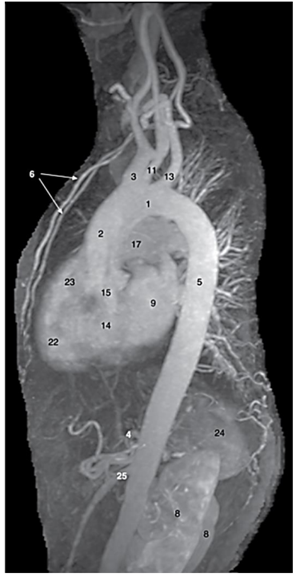

Observe a imagem a seguir.

Os números 9, 13, 14, 17 destacados nessa angiografia por ressonância equivalem às seguintes estruturas: